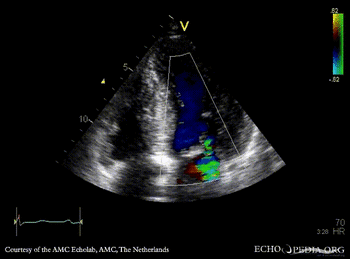

PSAX: severe concentric hypertrophy of left ventricle PLAX with Color Doppler: high velocity turbulent flow in LVOT, moderate mitral regurgitation